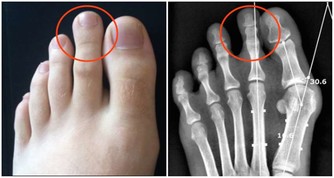

然而,當病情變得更加嚴重時,會導致腹痛、疲勞、極度疲倦、不明原因的體重減輕和虛弱。如果肝硬化發展,患者可能出現嚴重症狀,比如皮膚和眼白色變黃,腿部、腳踝、腳或肚子腫脹。然而等到那時候,就已經太晚了。